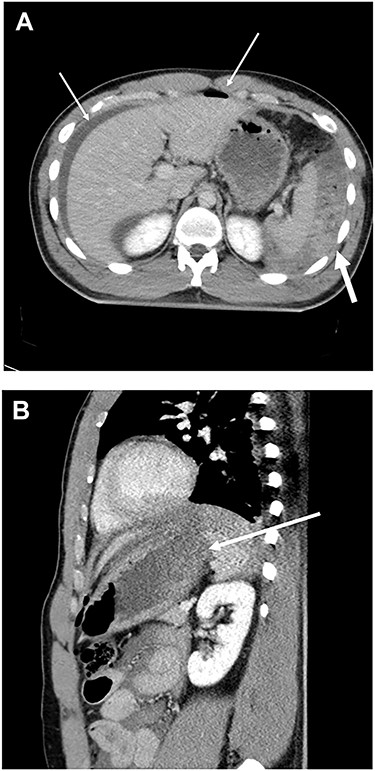

Our case was a 22-year-old man measuring 180 cm in height and weighing 86 kg. Two hours after eating a large amount of food, he was involved in a collision between his motorcycle and a motor vehicle. At the examination, he was alert and his vital signs were stable. The patient presented with an open skull fracture on the left forehead and described muscular defense throughout the abdomen. A whole-body computed tomography (CT) scan showed an open skull fracture reaching the left skull base (Fig. 1), and free air, ascites fluid, disruption of the gastric wall and a large amount of food residue behind the spleen (Fig. 2 and b). The head wound was first treated, and then, a laparotomy was performed on suspicion of a traumatic gastric rupture.

Head CT scan revealed open skull fracture reaching the left skull base (arrow) and mild brain contusion.